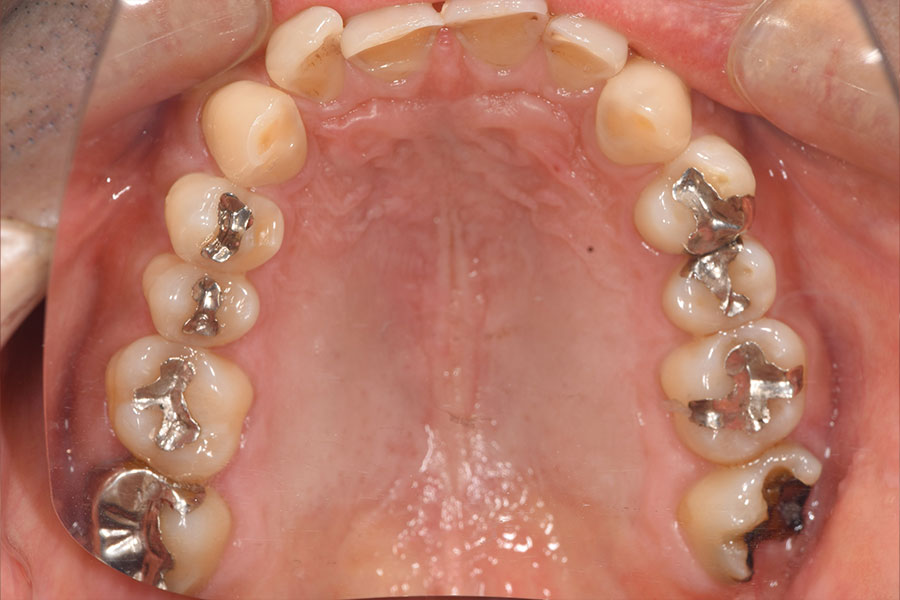

Before -上顎-

After -上顎-

| 施術内容 | 金属アレルギー予防を目的に、金属フリーの自費補綴へ変更。適合性・清掃性・審美性の向上が得られています。 |

|---|---|

| 治療期間 | 約4ヶ月 |

| 費用 | ハイブリットクラウン ハイブリットインレー 693,000円 |

| リスク・副作用 | 治療にともない、歯の破折や歯質の削合、場合によっては抜歯が必要となることがあります。また、金属や補綴物を除去する際に、完全に除去できない場合もあります。 |